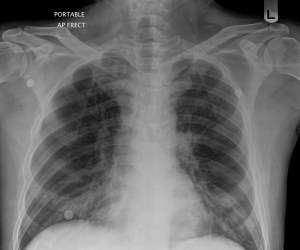

Below are his chest X-ray and a single cut of the CT thorax performed during the early stages of his illness.

The rest of the CT thorax essentially showed the same findings: ground glass changes throughout all lobes of his lungs.